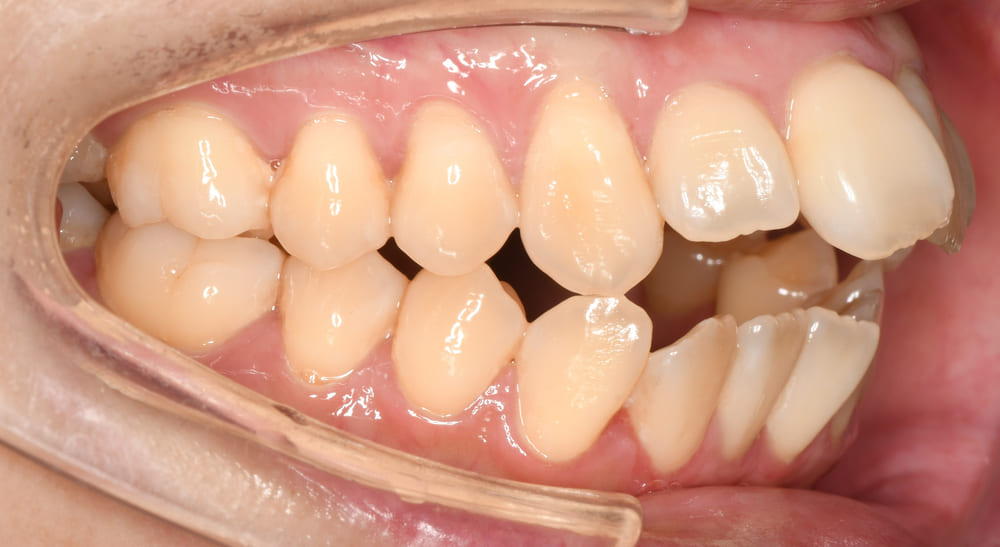

右側の写真では、

という、典型的な開咬パターンが確認されました。

通常であれば外科手術を行うべき症例でしたが「外科手術を行わず矯正治療のみにしたい」との患者さまのご希望がありました。

そこで慎重に3Dデジタル矯正での精密検査及び診断を経て、私の経験上から、矯正のみでも可能であると判断いたしました。

しかしながら外科手術を行わない、矯正単独治療でのリスク(主に後戻り)がありますので、そこについてしっかりと説明をさせていただき、リスクを理解していただいたうえで治療を開始しました。